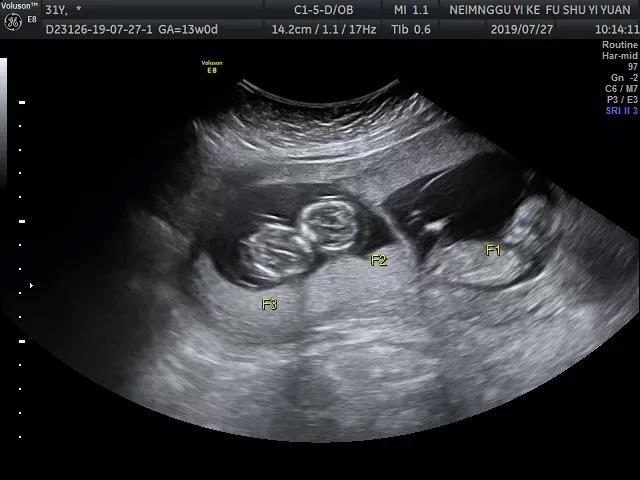

小杨婚后多年一直未孕,抱着最后试试看的心态就诊于我院生殖医学中心,生殖医学中心主任陈秀娟团队根据小杨的情况先后给予促排卵等多项治疗后半个多月来院检查,彩超提示:宫内早孕,3胎妊娠。

一下子怀上3个宝宝,这个结果让小杨一家既高兴又难过,因为在进行产检的时候,超声诊断科福林团队发现其中两个胎儿存在胸腹联体畸形,陈秀娟和小杨沟通,对怀上三胞胎的孕妇而言,发生妊娠并发症的风险大幅上升,而胸腹联体畸形是一种复杂而罕见的畸形,为了母婴安全,及时减胎十分必要。

术中照片